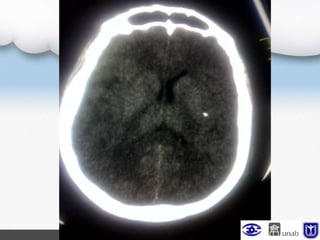

TAC cerebral (UCI)

Neurocirugía

Craniectomía Urgente

Injerto de meninge espinal

Se observa fungus cerebral leve